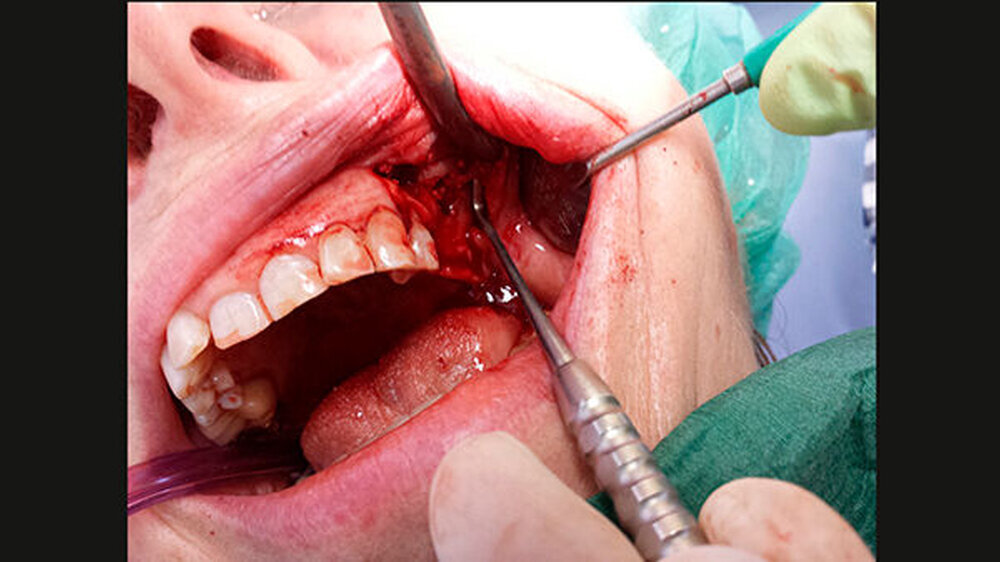

So planten wir für den März 2014 einen Sinuslift mit Augmentation und die Insertion zweier Implantate. Während dieses Eingriffs wurde ein Defekt in der buccalen Sinuswand deutlich sichtbar. Anscheinend bindegewebig war die Schneider`sche Membran durch den Knochendefekt mit der Wangenschleimhaut verbunden (Abbildung 1). Nach Durchtrennung des Gewebes und einer Abdeckung des Durchgangs mit einer resorbierbaren Membran wurde synthetisches Knochenersatzmaterial eingebracht und die Operation wie ursprünglich vorgesehen durchgeführt. Seither ist die Patientin beschwerdefrei.